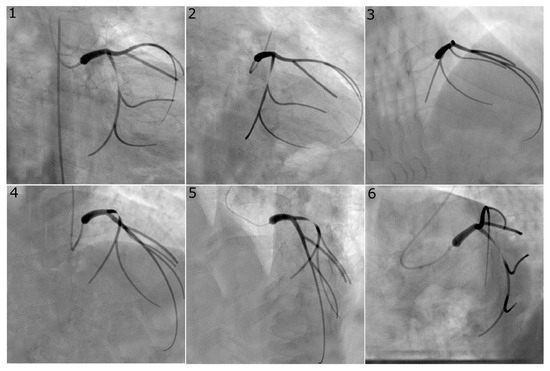

Figure 3.

Virtual angiogram for all views of the left coronary system with an eccentric stenosis of type “8040” in the LAD. Views , and were used to reconstruct this vessel as they are usually selected in the catheterisation laboratory since they avoid vessel overlap and excessive foreshortening for the vessel of interest.

Figure 2 and Figure 3 show representative examples of virtual angiograms generated for the two coronary arteries considered in this study. Figure 2 shows the case in which a concentric stenosis, of diameter reduction, affects the LCX. This case is included here for theoretical interest as it allows for an appreciation of the severity of a stenosis of this diameter reduction, but it is of smaller concern to the clinical community, due to the certainty of its severity. Figure 3 shows the case in which the LAD is affected by stenosis, this time of the eccentric type, with diameter reductions of and in the two orthogonal directions. This case shows how eccentric stenoses can appear differently in different views, and showcases that the choice of the view pair can result in either underestimation or overestimation of the severity of the stenosis (thus, overestimating or underestimating the radius, respectively).

The accuracy of the reconstruction of the vessel radius at the stenosis location was expected to be closely related to the accuracy of the computed vFFR. Greater variation of this metric was observed with choice of image pairs with a range of maximum absolute error from 0.07 mm to 0.20 mm for the LCX and 0.15 mm to 0.24 mm for the LAD. There was no clear relation between absolute error and the stenosis severity; as a result, the percentage error in the stenosis radius tended to increase for larger-percentage diameter reductions. The error in stenosis reconstruction was typically larger for cases with eccentric stenosis, as expected, due to the different views showing different vessel radii depending on the orientation of the eccentricity. Indeed, as visible in Figure 3, which reports a case of eccentric stenosis in the LAD, the vessel radius appears significantly larger in views 4 and 5, compared to, for example, views 1 and 2. Our software estimates the vessel radius from each of the two angiographic views and averages the two values; the reconstructed local lumen will have a circular shape with a radius equal to that averaged value. It is possible for two views to simultaneously fail to capture the peak value of stenosis, thus obtaining a larger error in the radius estimation and therefore in the vFFR.